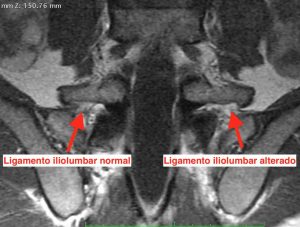

Podemos empezar con una radiografía simple de columna lumbar, para valorar alguna asimetría en el último segmento vertebral a nivel de las apófisis transversas. Pero muchas veces es necesario una resonancia de pelvis o incluso un TAC.

Es muy difícil que en los informes de estas pruebas se mencione alguna alteración de este ligamento o de los huesos. En la gran mayoría de ocasiones si los pacientes son jóvenes serán informados como normal.

Es importante que el especialista mire las imágenes y pueda comprobar si existe alguna diferencia aunque parezca sutil.

Flechas rojas: Ligamento iliolumbar